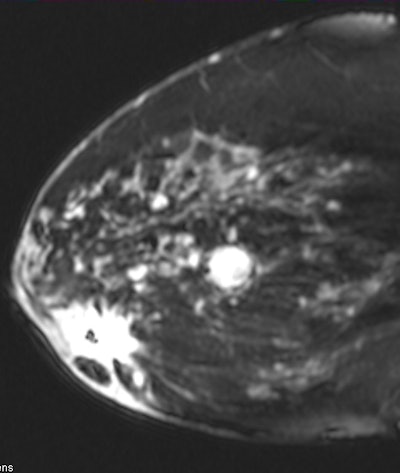

Known subareolar invasive ductal carcinoma as seen on sagittal MRI. All images courtesy of Dr. Stamatia Destounis.

Known subareolar invasive ductal carcinoma as seen on sagittal MRI. All images courtesy of Dr. Stamatia Destounis.Destounis and colleagues identified 115 malignant cancers (42%) in the retrospective review. Of those, 83 lesions were in the ipsilateral breast and 32 were in the contralateral breast. The group also found 127 benign lesions and 29 atypical/high-risk lesions.